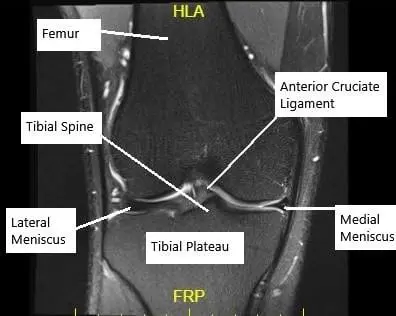

MRI of the knee in the coronal section showing an intact ACL.

The ACL is one of the major ligaments in the knee joint, crucial for stability during activities like running, jumping, and pivoting. It connects the thigh bone (femur) to the shin bone (tibia) and prevents excessive forward movement of the tibia in relation to the femur. Without a functioning ACL, the knee can feel unstable, making it difficult to perform everyday tasks and sports activities.

The anterior cruciate ligament connects the thigh bone to the shin bone. Its main role is preventing the shin bone from moving too far forward and controlling rotation during running, pivoting, or jumping. Without the anterior cruciate ligament, the knee can feel loose and unstable.

Imaging such as an MRI is used to confirm an anterior cruciate ligament tear and evaluate the surrounding structures. The MRI shows the condition of the ligament and helps guide treatment planning.